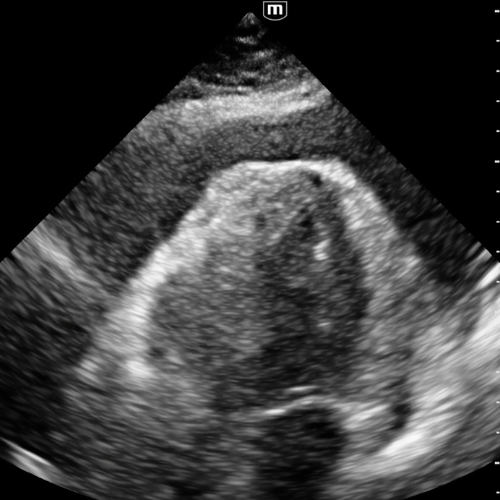

Vue sous-costale

Fenêtre prioritaire chez le patient instable ou en arrêt.

Le liquide apparaît comme une bande noire entourant le cœur, le plus souvent postérieure.

C’est ici que l’on détecte les premiers signes de collapsus du ventricule droit ou de l’oreillette droite.